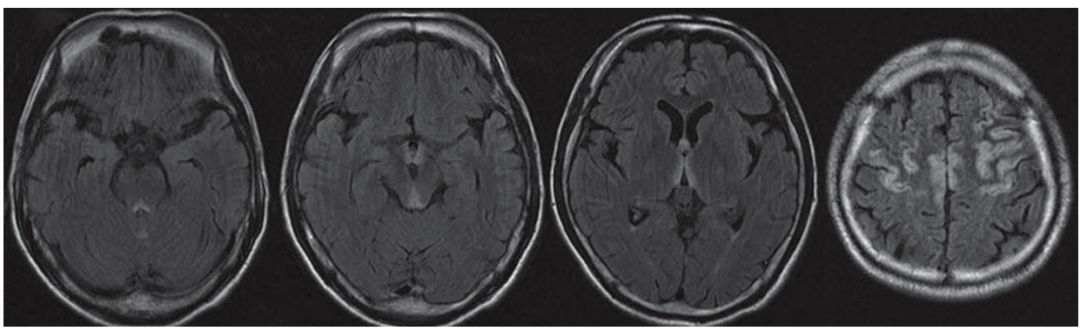

颅脑MRI轴位示:双侧乳头体、导水管周围、

穹窿、丘脑背内侧及大脑皮层对称性高信号

简称MBD,是一种罕见的以胼胝体脱髓鞘和坏死为主要病理特征的慢性酒精中毒相关性疾病。这种病的临床表现无特异性,急性起病者可出现严重的意识障碍和认知损害,常危及生命;慢性起病者主要表现为进行性痴呆。

急性期典型影像学表现为“三明治征”,即:矢状位上的病变主要位于胼胝体中层,上层和下层正常。以胼胝体全段受累更为常见。急性期后,胼胝体异常信号逐渐消退。

慢性期表现为胼胝体萎缩,伴局灶性长T1、T2信号,可能反映了进行性脱髓鞘、局灶性坏死和囊变。如果病变出现在胼胝体外,则以皮质下白质最为多见。

颅脑MRI矢状位FLAIR示胼胝体压部高信号(A)

DTI示同一部位胼胝体横向纤维受损(B)

DWI和ADC示胼胝体压部细胞毒性水肿(C、D)

颅脑MRI、DWI示:

双侧大脑半球皮层下白质、

胼胝体、双侧小脑中脚高信号